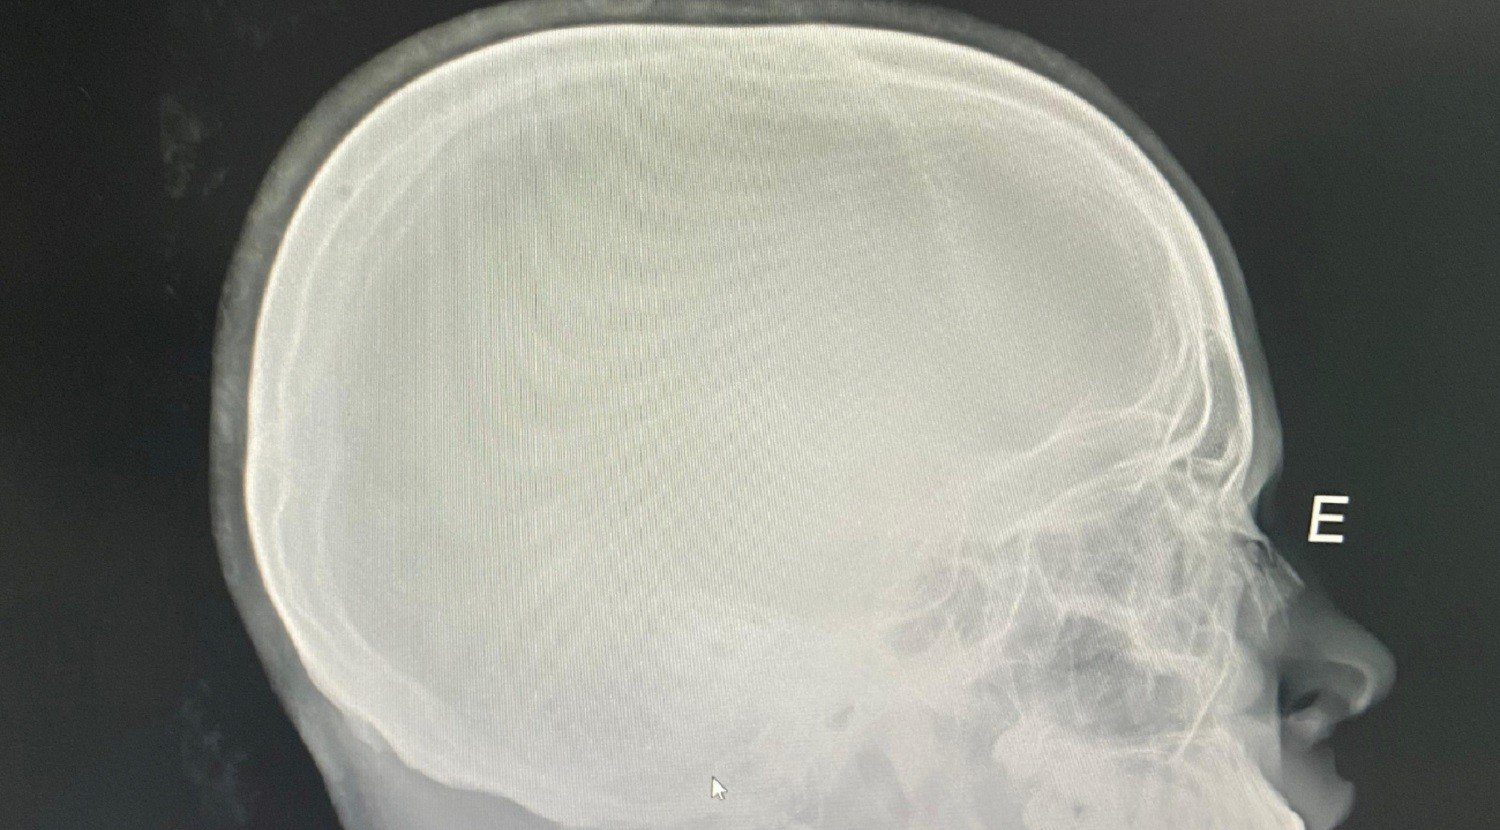

A vítima passou por cirurgia no nariz em 11 de março, em Porto Nacional. O caso é investigado pela Polícia Civil; de acordo com a Secretaria da Segurança Pública (SSP), o inquérito tramita sob sigilo por envolver menores de idade.